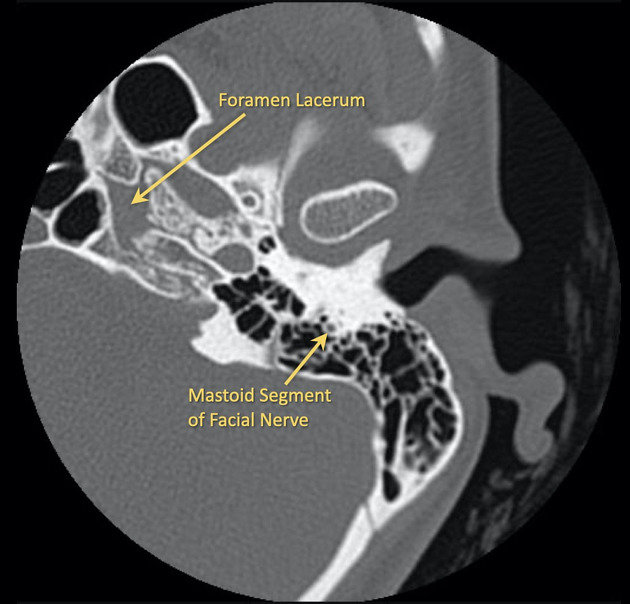

Brain CT scans can provide more detailed information about brain tissue and brain structures than standard X-rays of the head, thus providing more data related to injuries and/or diseases of t...